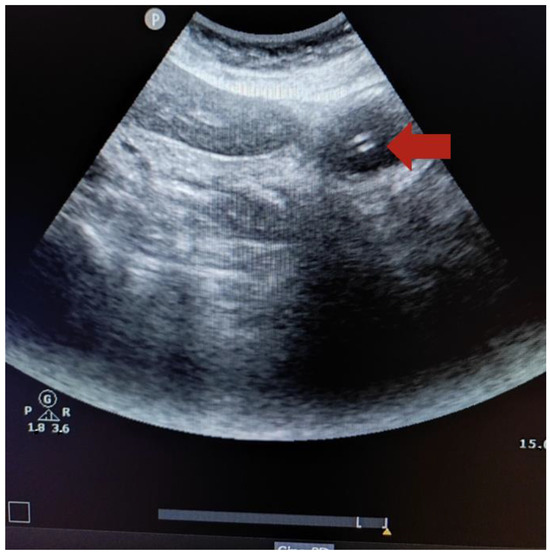

2.6. Technique to Perform the Ultrasound